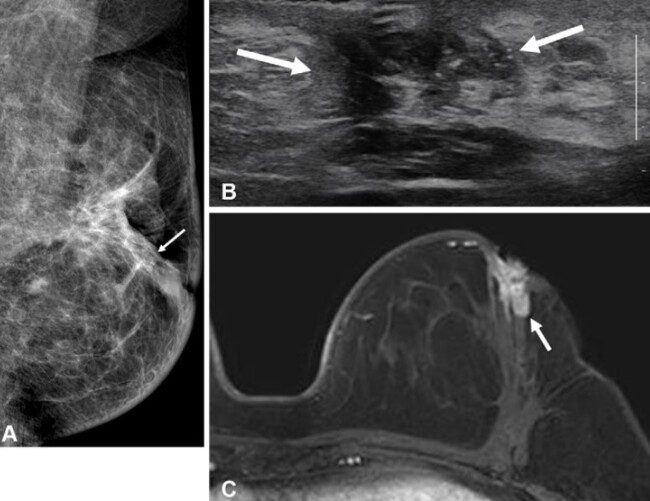

유방 MRI는 유방암 검사 중 가장 민감도가 높아 유방촬영술과 초음파에서 놓친 종양도 탐지할 수 있다. 그러나 젊은 환자의 수술 전 MRI 검사가 장기적 예후에 미치는 영향, 특히 호르몬 수용체 상태에 따른 영향은 명확히 규명되지 않았다. 수술 전 MRI 검사를 시행하지 않은 50세 이하 환자의 수술 2년 후 유방 영상 검사 결과. (A)유방촬영술 (B)유방초음파에선 동측 유방 내 재발이 발생함. (C)MRI에선 발견되지 않음